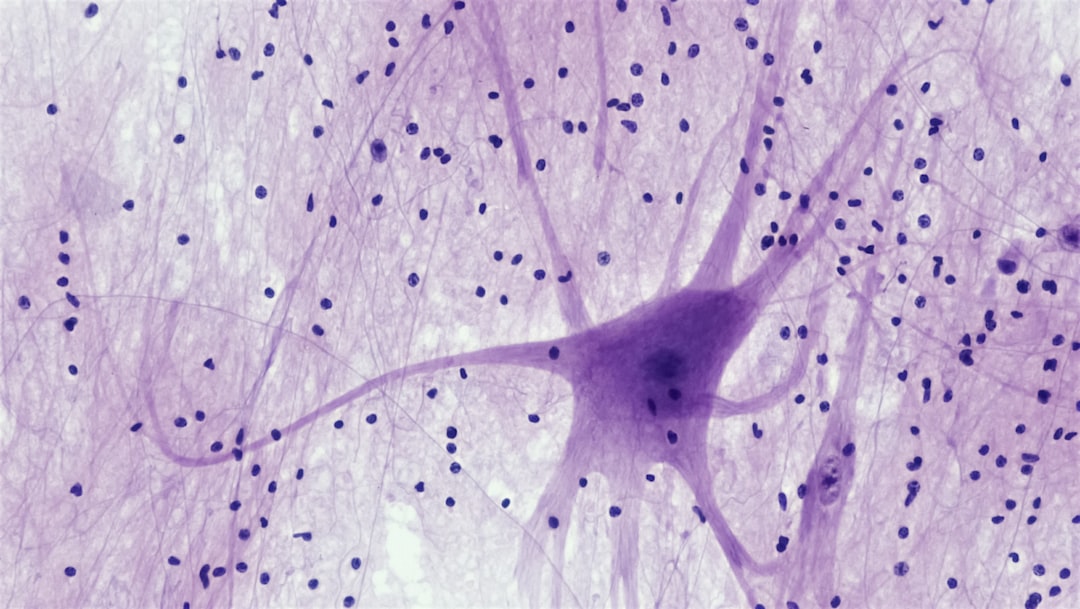

당뇨 발저림은 당뇨병 환자들 사이에서 흔히 나타나는 증상 중 하나로, 주로 발에 저림이나 감각 이상의 형태로 나타납니다. 이 증상은 당뇨병으로 인한 신경 손상에 기인합니다. 특히 고혈당이 지속되면서 혈관이 손상되고, 그로 인해 신체의 신경이 제대로 기능하지 않게 되는 것입니다. 개인적으로 경험해본 바로, 이러한 증상은 삶의 질을 크게 저하시킬 수 있습니다. 우리는 발저림이 있을 때, 간단한 일상생활조차 힘들게 느껴질 수 있으니까요.

당뇨 발저림의 발생 원인은 주로 높은 혈당과 관련된 신경 손상입니다. 혈당이 고갈되면 신경 조직이 손상되기 시작하고, 이는 신경 말단의 기능 저하를 초래합니다. 물론, 이러한 신경 손상은 전체 신경계에 영향을 미치며, 종종 제가 생각하기에도 이는 매우 불편한 경험으로 이어집니다.

게다가 당뇨 환자들에게서 자주 나타나는 가벼운 우울감이나 불안도 당뇨 발저림의 원인으로 작용할 수 있습니다. 제가 직접 경험한 바에 따르면, 스트레스와 정신적 불안감이 만날 때 신체적 불편이 두 배로 증가하는 것 같았습니다. 신경과학적으로도 증명된 바와 같이, 정서적 요인이 신경계의 이상 반응을 유발할 수 있다는 점은 반드시 고려해야 합니다.